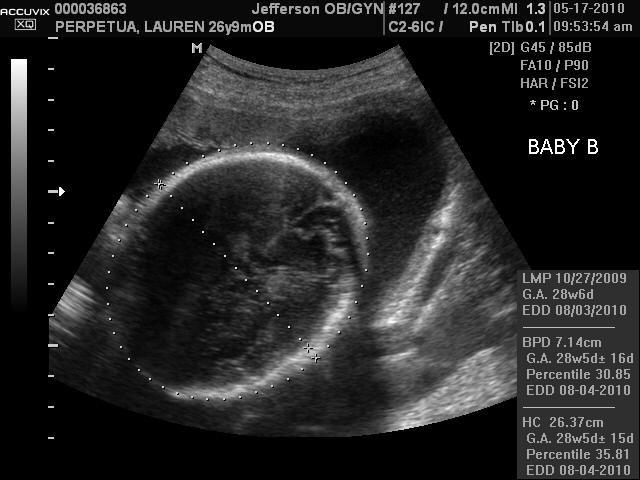

I am 29 weeks pregnant! We had an ultrasound on Monday and received excellent news- both babies are growing congruently- meaning they are growing together! Each baby weighs about 2 ½ lbs, and they are both head down in what they call vertex position. Because of their positioning, the doctor said I should plan on delivering naturally at this point. Obviously, like with any pregnancy, a C-Section might be necessary, but the odds have gone down. The doctor also told us that twins reach term at 35 weeks, where a singleton baby will reach term at 37 weeks. Basically meaning that although they are not ready to come out at 35 weeks, if they were born then they would be pretty normal little infants. When we asked why they develop two weeks faster than singletons, the doc said it is because twins are, and I quote “scrappy.” They are scrappy because they have had to compete with each other for nutrients and space the entire pregnancy- so they develop quicker. It just amazes me. Joey and I can’t wait to meet these scrappy little guys!

During the ultrasound, Tank turned his head towards the ultrasound wand and we could clearly see his face for a split second. It was amazing. The ultrasound tech was even impressed. Below are a few pictures from the ultrasound, but it is harder to see them because they are getting so big… so you kind of got to piece them together. The first picture is of Tank's face. The second picture is the top of Dozer's head.